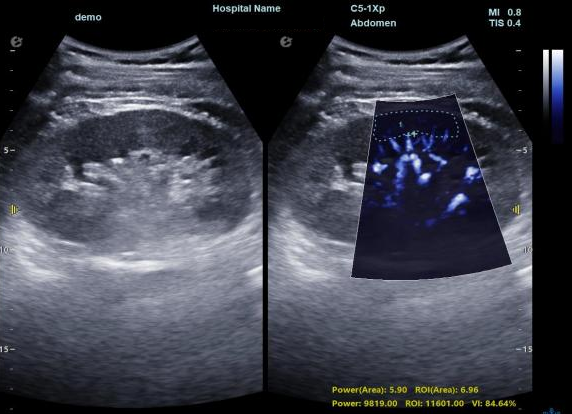

3) 通过血管指数(VI)定量评估局部血管密度,以定量化数据实时监测血流灌注情况,预判肾功能恢复情况;

肾脏的灌注评估,RI/VI量化数据

超微视血流显像评估肾移植术后灌注情况

这一项无创、无辐射操作简便且无需造影剂的黑科技,相当于用"高速摄像机"记录血液细胞的运动轨迹,让血管并发症"无处遁形。